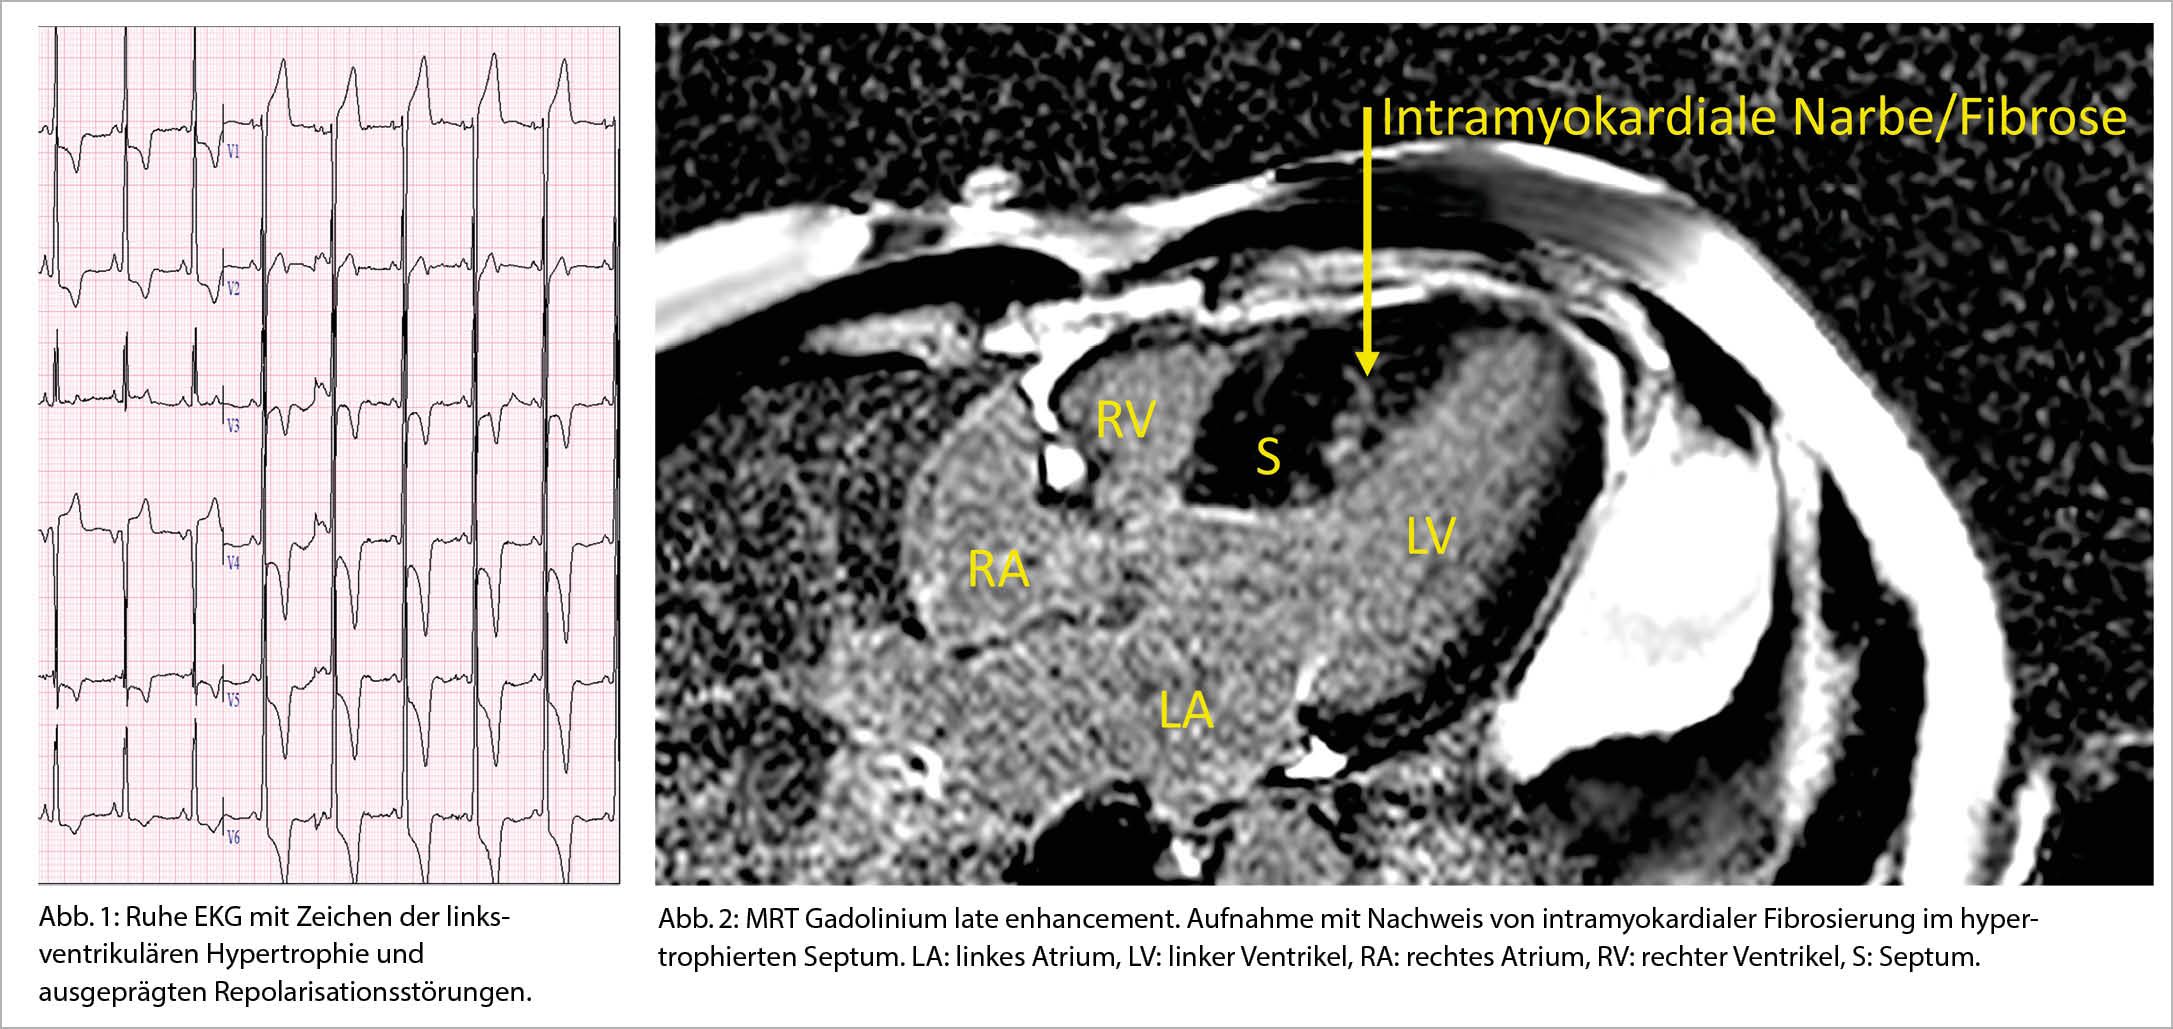

Der 49-jährige Patient war initial wegen einer Lumbago hospitalisiert. Anlässlich der klinischen Untersuchung liess sich ein auffälliges 3/6 Systolikum auskultieren, und es zeigte sich ein pathologisches Ruhe-EKG (Abb. 1). In der transthorakalen Farbdopplerechokardiographie zeigte sich eine schwere Hypertrophie des linken Ventrikels mit einer ausgeprägten Verdickung insbesondere des interventrikulären Septums bis 25 mm. Diese Hypertrophie führte zu einer systolischen Vorwärtsbewegung des vorderen Mitralsegels (systolic anterior movement, SAM) und als Folge davon zu einer Mitralklappeninsuffizienz, sowie zu einer Obstruktion im linksventrikulären Ausflusstrakt (LVOT). Die Diagnose einer HOCM wurde mit einer kardialen Magnetresonanz Tomographie (MRT) bestätigt, welche die schwere, septal betonte Hypertrophie bestätigte, und eine zusätzliche lokalisierte Hypertrophie inferoapikal objektivierte. Insbesondere in diesen hypertrophierten Arealen zeigte sich bei den «Late Gadolinium Enhancement» Sequenzen eine typische, diffuse intramyokardiale Fibrosierung (Abb. 2). Im 24-Stunden Holter-EKG zeigten sich keine relevanten Arrhythmien. Während ca. 5 Jahren bestand ein relativ stabiler Verlauf, der Patient beklagte jedoch eine zunehmende Anstrengungsdyspnoe und schliesslich auch relativ typische pectanginöse Beschwerden, welche sich durch diverse Medikamente (Betablocker, Ca-Antagonisten, Ranolazin) nicht adäquat behandeln liessen. Eine koronare Herzkrankheit wurde angiographisch ausgeschlossen. Echokardiographisch wurde eine weitere Progredienz der Befunde registriert. Es entwickelten sich schliesslich eine schwere Obstruktion im LVOT mit maximalen Druckgradienten unter Valsalva bis >200 mmHg, sowie durch den SAM auch eine schwere Mitralklappeninsuffizienz. Zur Verminderung des Druckes im LVOT wurde eine transkoronare Ablation der Septumhypertrophie (TASH) durchgeführt, welche jedoch nur kurz zu einer leichten Abnahme des Druckgradienten im LVOT, und zu keiner Besserung der Klinik führte. Aus diesem Grund erfolgte schliesslich eine chirurgische Myektomie und ein Mitralklappenersatz. Da es postoperativ zu einem kompletten AV-Block kam musste auch noch ein Schrittmacher implantiert werden. Seit der abgeschlossenen Rehabilitation zeigt der Patient nun jedoch einen erfreulichen Verlauf und auch die pectanginösen Beschwerden sind vollständig verschwunden.